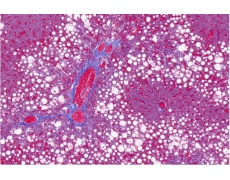

切片全景掃描(白光)